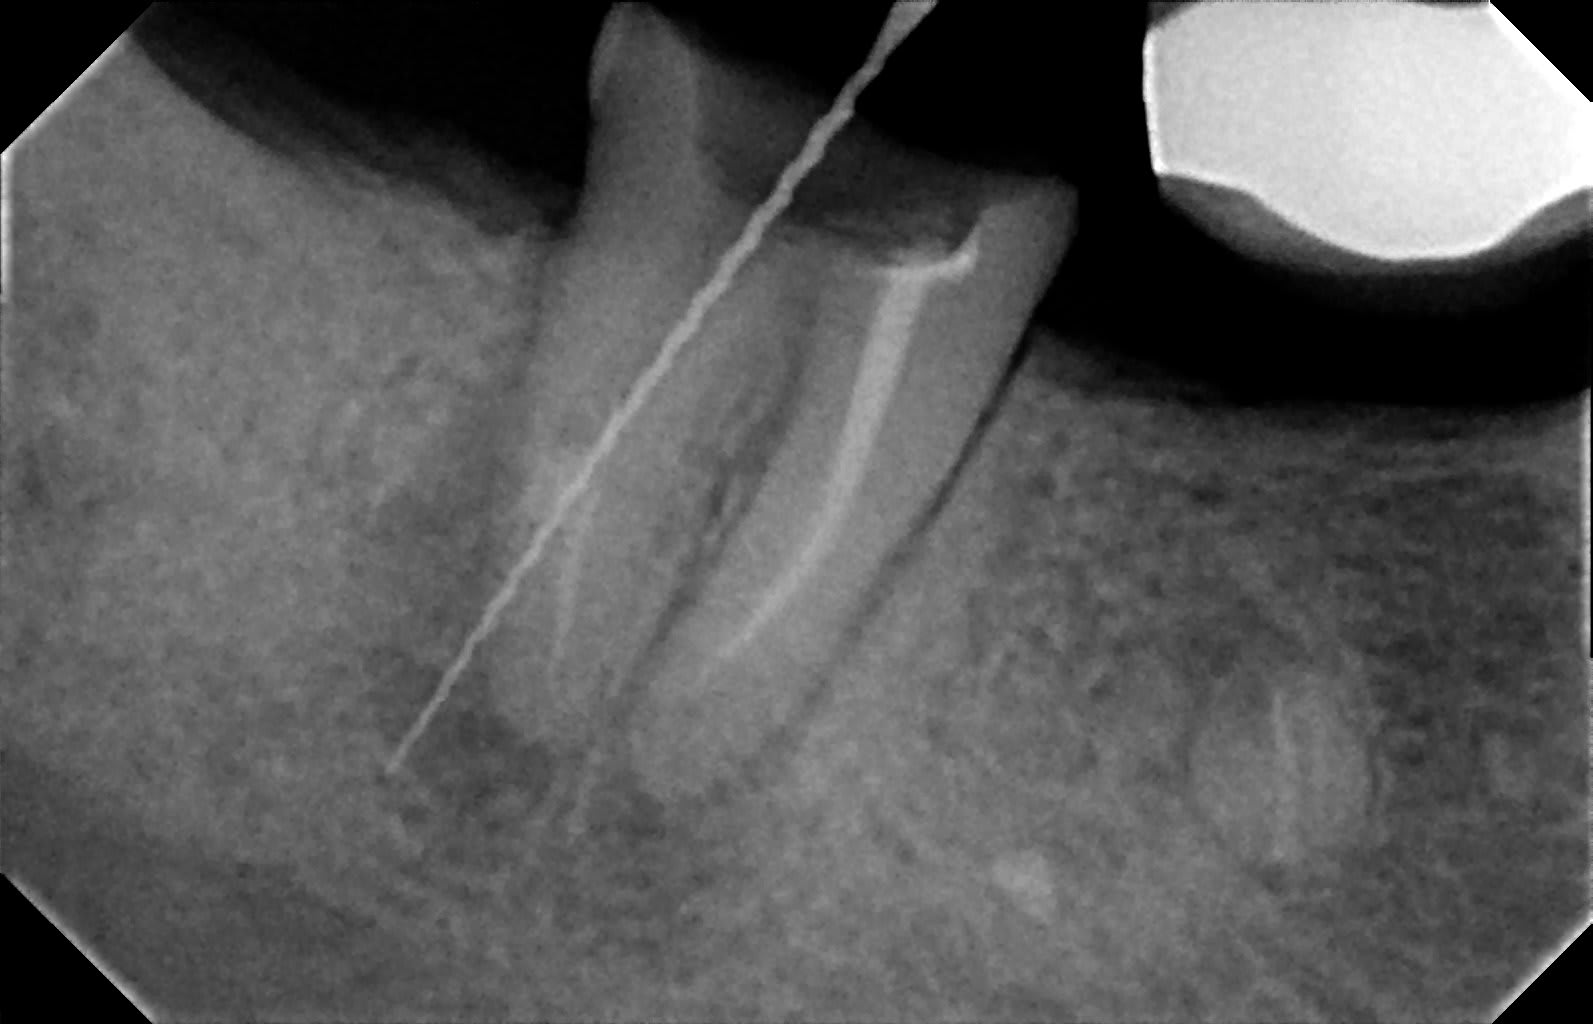

Une patiente consulte pour petite douleurs coté 40.

La 47 a un FM et est pilier de bridge 45-46-47.

Présence d'un granulome le long de la racine distale.

Je décide de tenter une reprise d'endo, on ne sait jamais vu l'importance de la dent.

Une fois le FM enlevé, la première broche révèle un petit saignement.

Ci joint une radio avec une broche qui montre une perforation.

ç est plus un cas de racine cassée que d endo , non ?

+1 fracture due au tenon

+1 racine fracturée, et sympa la racine devant

Fracture ou fausse route lors de l'utilisation du forêt...

Ensuite.... Y'a deux belles péches apicales...

La racine distale est cuite.

Mais tu peux toujours garder la mésiale comme support, possible mais risqué, à voir dans le contexte global.